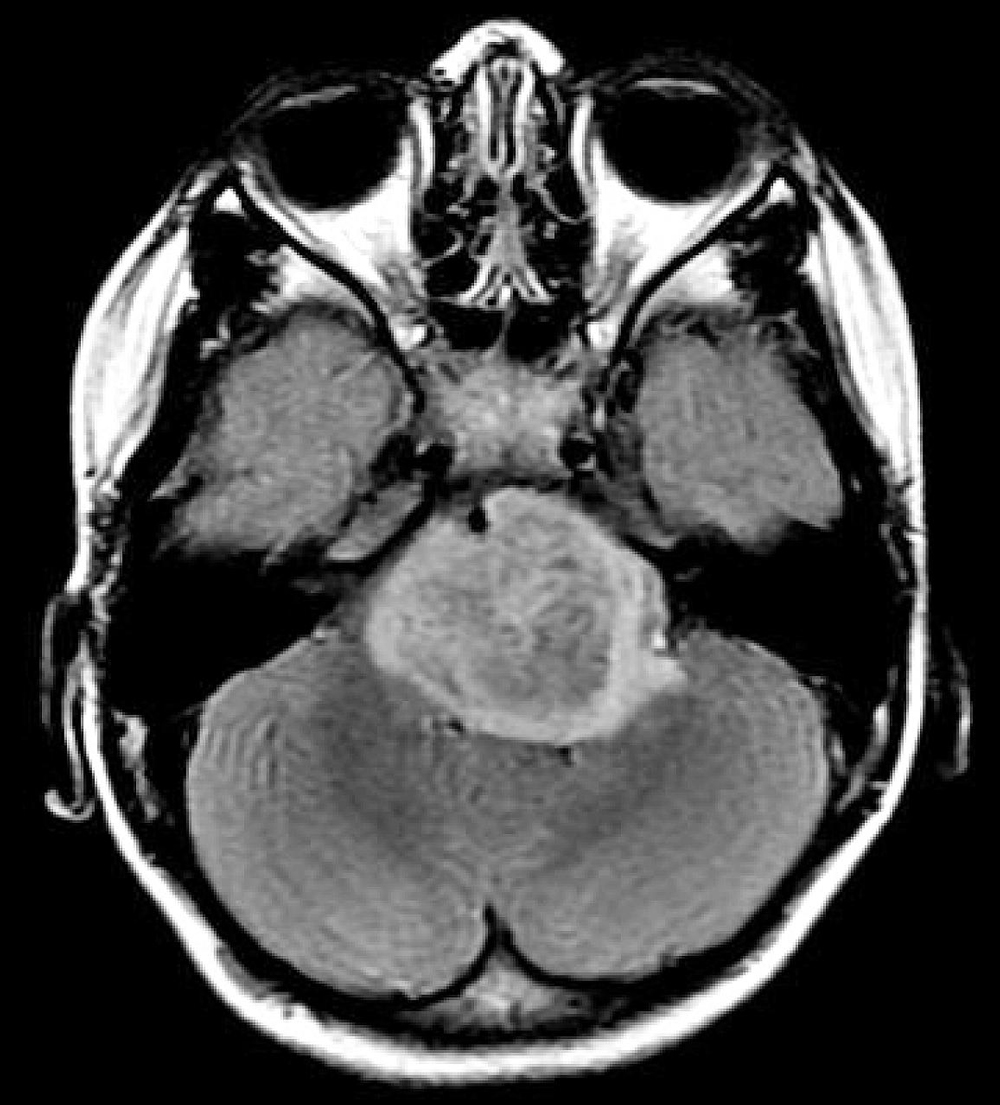

Foto: Las pruebas genéticas de muestras de tumores cerebrales pediátricos podrían ayudar a guiar el diagnóstico y el tratamiento. Crédito: Institutos Nacionales de Salud de Estados Unidos.